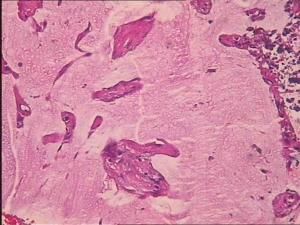

與其他部位畸胎瘤一樣,胃畸胎瘤含有三個胚層成分,這些成分大部分主要是成熟組織,但是有些神經組織顯示原始未成熟結構。不同在於一般認為本病是良性的,而且從發現發展到惡性。儘管通常見到未成熟的神經組織,少數病例病理報導為未成熟型畸胎瘤,但臨床上都證實為良性,單純的腫瘤切除,而不加用化療效果良好。年齡、性別和大體形態、梗阻症狀、胃腸道出血和X線表現都不是本病惡性的可靠徵象。專家分析向胃內生長的腫瘤由於黏膜潰瘍可引起嘔血和黑便症狀。